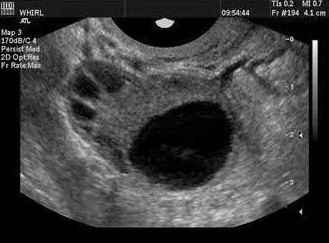

卵泡的正常生長受卵巢自身功能和下丘腦-垂體-卵巢軸以及中樞神經(jīng)系統(tǒng)、內(nèi)分泌系統(tǒng)的復(fù)雜影響。一般情況下,精子的壽命為2--3天,而排卵后卵子的壽命較短,15小時即會逐漸衰老;因此,排卵前兩天至排卵后10小時是受孕的關(guān)鍵時間。當(dāng)卵泡直徑>10mm時,稱優(yōu)勢卵泡;卵泡直徑達(dá)>18mm時,稱成熟卵泡。

一般認(rèn)為成熟卵泡直徑在18-25mm,妊娠機(jī)率較大,卵泡直徑<18mm則不易妊娠。所以說卵泡發(fā)育不良,不能正常排卵或者排出的卵子質(zhì)量不好,都會影響正常的受孕生育。